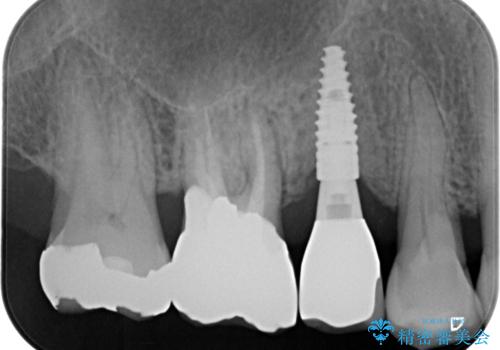

失った奥歯のインプラント治療

- 失ったままで放置していたインプラント治療を希望され来院されました。

抜歯後から十分に時間が経過しており、すぐにインプラントの埋入を計画できる状態です。

「失った1本の歯の機能回復を行うだけでもずいぶん咬めるようになった。」、と咬合機能の回復を実感していただくことができました。